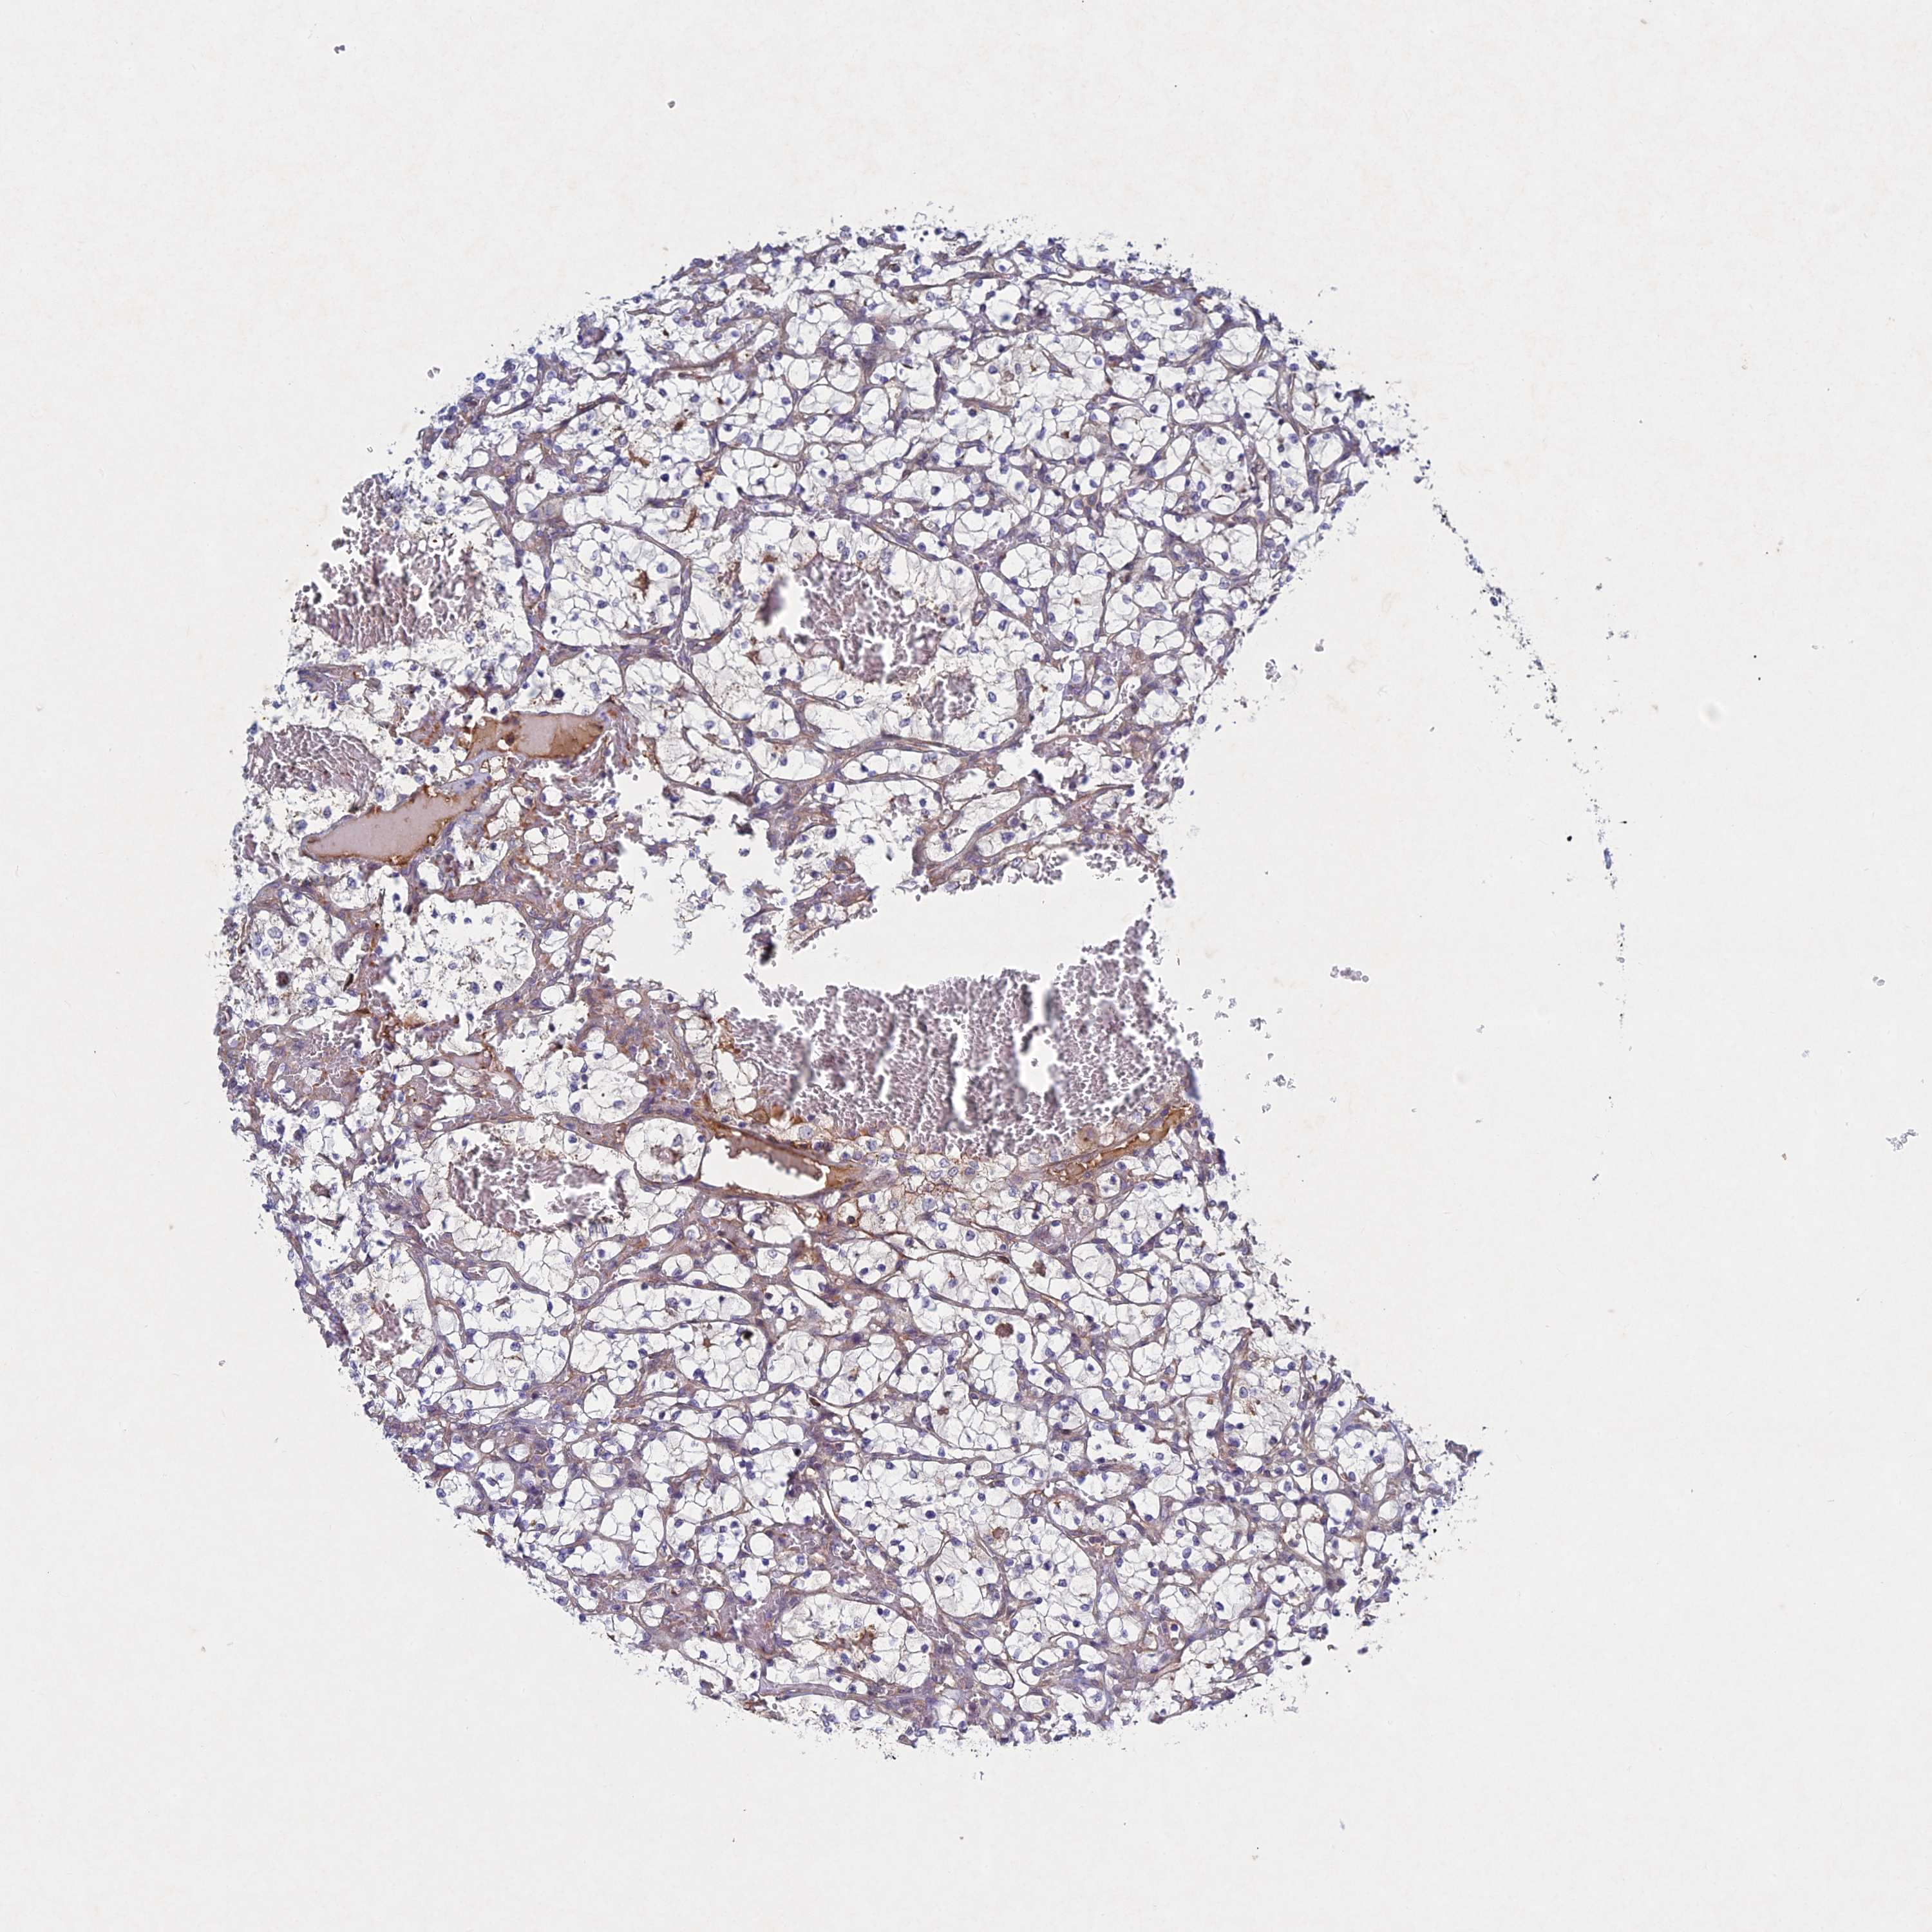

KIDNEY RENAL PAPILLARY CELL CARCINOMA (TCGA) - Interactive survival scatter ploti

The Survival Scatter plot shows the clinical status (i.e. dead or alive) for all individuals in the patient cohort, based on the same data that underlies the corresponding Kaplan-Meier plots. Patients that are alive at last time for follow-up are shown in blue and patients who have died during the study are shown in red.

The x-axis shows the expression levels (FPKM) of the investigated gene in the tumor tissue at the time of diagnosis. The y-axis shows the follow-up time after diagnosis (years). Both axes are complimented with kernel density curves demonstrating the data density over the axes. The top density plot shows the expression levels (FPKM) distribution among dead (red) and alive patients (blue). The right density plot shows the data density of the survived years of dead patients with high and low expression levels respectively, stratified using the cutoff indicated by the vertical dashed line through the Survival Scatter plot. This cutoff is automatically defined based on the FPKM cutoff that minimizes the p-score. The cutoff can be changed by dragging the vertical line or by entering a cutoff value in the square labeled "Current cut-off".

Under the Survival Scatter plot the p-score landscape (black curve; left axis) is shown together with dead median separation (red curve; right axis). Dead median separation is the difference in median mRNA expression between patients who have died with high and low expression, respectively. It is calculated as follows: median FPKM expression of dead patients with high expression - median FPKM expression of dead patients with low expression. This is intended to aid the user in visually exploring custom cutoffs and the associated p-scores and dead median separation.

Individual patient data is displayed and can be filtered by clicking on one or more of the category buttons on the top of the page. Categories describing expression level and patient information include: high, low, alive, dead, female, male and tumor stages. The scale of the x-axis can be toggled between linear and log-scale by clicking on the "x log" button. Mouse-over function shows TCGA ID, patient information and mRNA expression (FPKM) for each patient.

& Survival analysisi

Kaplan-Meier plots summarize results from analysis of correlation between mRNA expression level and patient survival. Patients were divided based on level of expression into one of the two groups "low" (under cut off) or "high" (over cut off). X-axis shows time for survival (years) and y-axis shows the probability of survival, where 1.0 corresponds to 100 percent.

PTHLH is potential prognostic, high expression is unfavorable in Kidney Renal Papillary Cell Carcinoma (TCGA)

Best expression cut offi